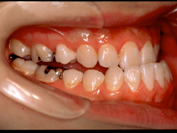

1) 主訴 下あごが出ている、前歯で咬むことができない、しゃべりにくい

2) 診断名 顎変形症(下顎近心変位)

3) 初診時年齢 22歳

5) 抜歯 新規抜歯はなし(ただし上顎左右の第一小臼歯は初診時には既に抜歯されていた)

6) 治療期間 開始時から装置装着まで3か月、術前矯正期間5か月、術前矯正期間3か月、保定期間3年

合計3年11か月

8) 考えられる治療効果 咀嚼能力および能率の向上、構音機能の改善、口唇の閉鎖機能の改善、側貌を含め

口唇等の審美性の改善